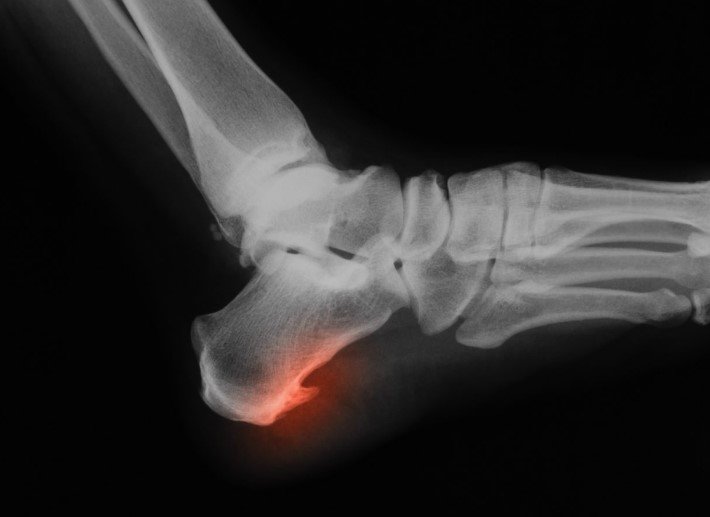

Болезнь редко сопровождается внешними проявлениями. Пятка при шпоре может выглядеть нормально. Патологию травматологи-ортопеды диагностируют по результатам опроса пациента и рентгену. Если снимок не дает ясной картины, дополнительно могут назначить УЗИ и анализы крови. С их помощью исключают другие патологии, вроде ревматоидного артрита.